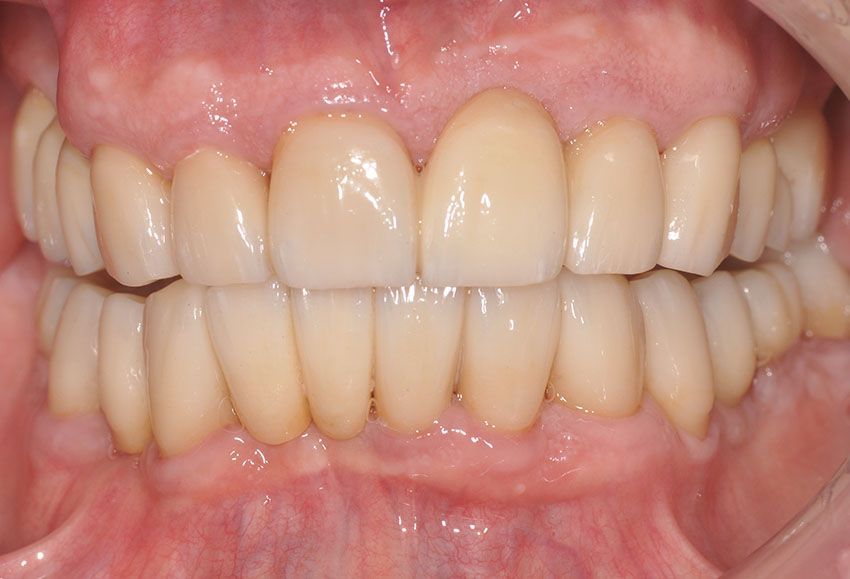

Diresti mai che è una protesi?

Il nostro obiettivo è restituire un sorriso naturale e armonioso attraverso protesi stabili ed integrate, ricorrendo alla protesi mobile solo quando non esistono alternative valide.

Ogni manufatto viene studiato sulla base delle caratteristiche del volto, del sorriso e dell’occlusione, per restituire funzionalità e comfort, esaudendo le aspettative estetiche di ogni paziente.

Le protesi fisse su impianti in particolare, offrono stabilità nel tempo, una resa estetica elevata, una sensazione naturale durante la masticazione, nonché l'integrazione ottimale con denti e tessuti. Il paziente viene accompagnato in ogni fase, dalla pianificazione alla finalizzazione del lavoro, con

pazienza, trasparenza e professionalità.